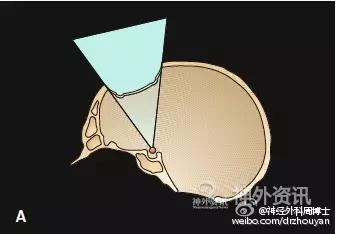

图示额颞开颅-额下入路的发展历程。注意观察皮肤切口和骨瓣大小的变化。A. Dandy的额颞入路;B. Yasargil的翼点入路(应用显微外科技术);C. 眶上keyhole开颅入路:显露Yasargil翼点入路的额底部分,显著缩小了开颅范围,也显著降低了颅内、外的手术创伤。

A. 标准的大范围开颅,暴露术野深部病变的视角呈漏斗型; B. 这种传统的大范围开颅方法可以被视为若干keyhole手术入路的整合;C. 只要选择正确的小骨窗路径,手术视角呈扇形扩大。路径越短,手术视角越窄;而路径越长(术野深部病变),手术视角则越宽。这种路径选择方法,有时还可同时处理对侧的病变。